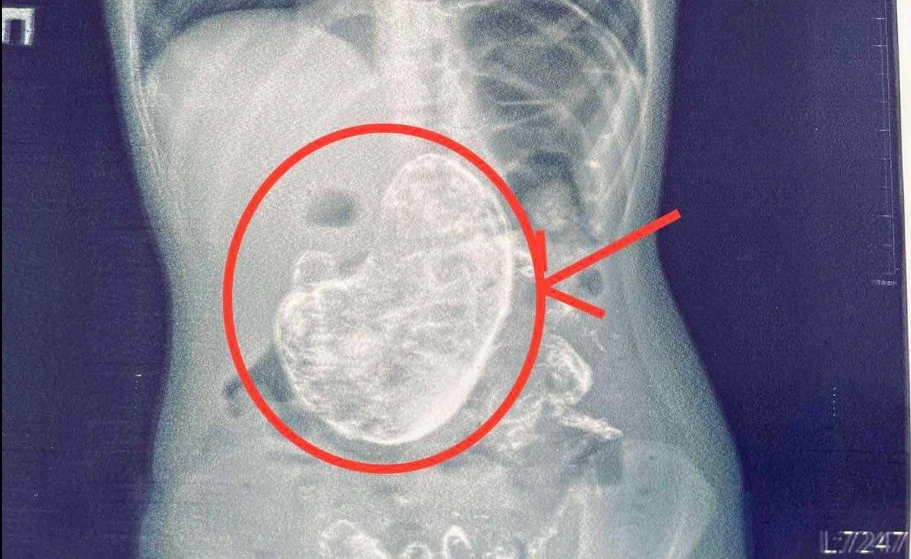

"Rtg дослідження шлунково-кишкового тракту допомогло виявити стороннє тіло в шлунку, а ФЕГДС підтвердила наявність тріхобезоару", – пояснює Тарас Мельник.

Завдяки злагодженій роботі команди гастроентерологів, анестезіологів і хірургів дитину успішно прооперували, а стороннє тіло, сформоване з волосся вагою 1 кг, видалили.